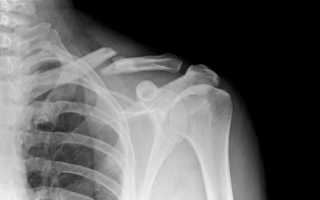

В современной травматологической практике встречаются повреждения диафиза, акромиального и грудинного конца ключицы. По характеру повреждения встречаются простые, оскольчатые, косые и кососпиральные виды повреждений.

Очень важно правильно диагностировать разновидность перелома, от этого напрямую зависит тактика выбранного лечения.

Часто под воздействием мышечной тяги, переломы ключицы осложняются смещением отломков. В таких случаях возникает риск развития опасных осложнений: повреждение нервных пучков и крупных сосудов, нарушение целостности плевральной полости, легких и кожи.

Диагноз ставится по данным рентгенологического обследования, компьютерной томографии, визуального осмотра пострадавшего и сбора анамнеза.